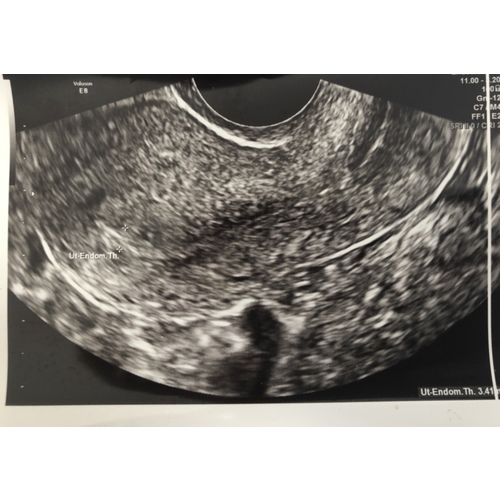

Volgens mij trekken ze hem toch over de hele dikte? Dat is dat de uitslag... ik heb toevallig nog een foto... 3.41 mm